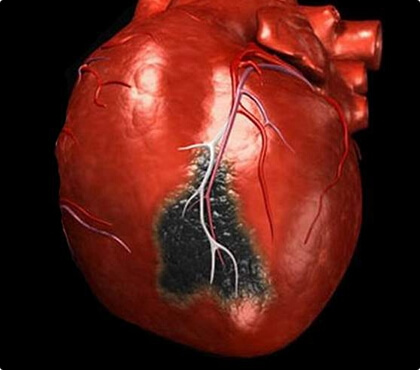

हृद्पेशीय रोधगलन

हृद्पेशीय रोधगलन

हृद्पेशीय रोधगलन

हृदय की मुख्य धमनी के माध्यम से रक्त के प्रवाह में रुकावट के कारण हृदय की मांसपेशी के हिस्से की मृत्यु से पूर्ण हृदय गति रुक सकती है।